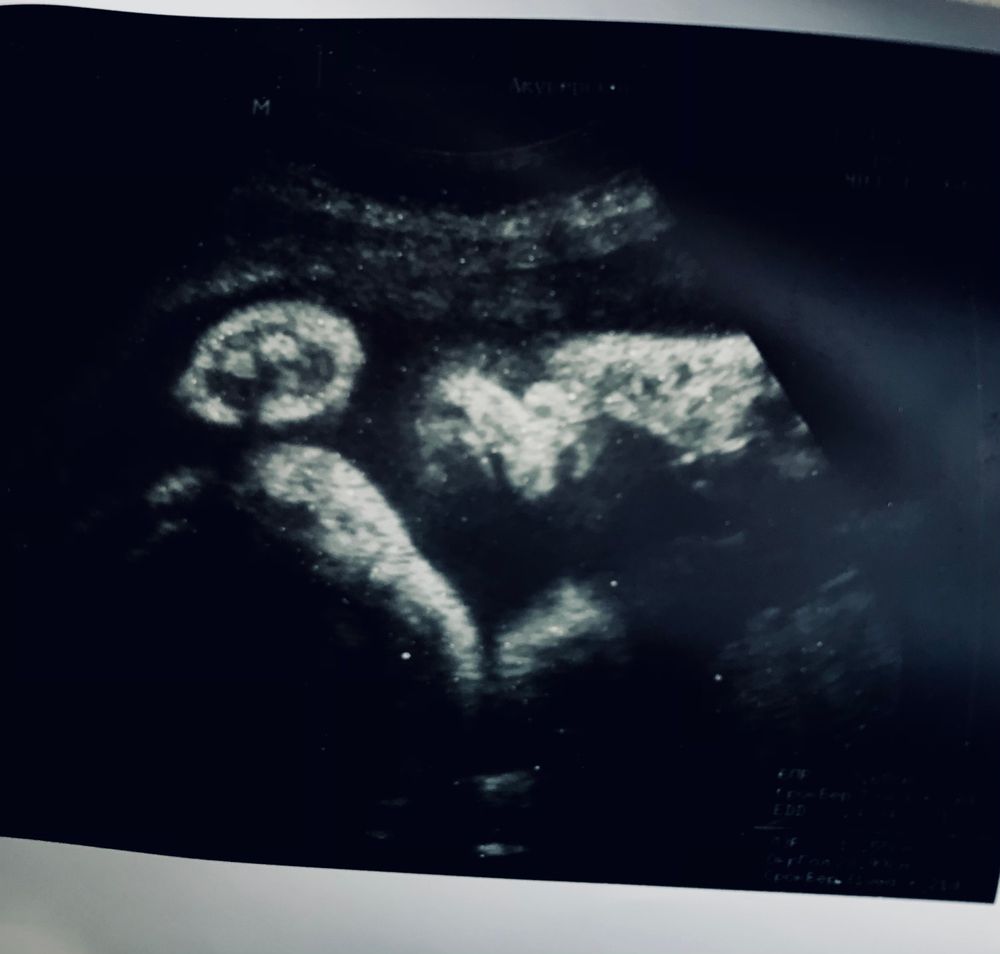

32 недели

Сегодня 32 недели по первому узи, по. М. в пятницу, как же быстро летит время....

В 31 недельку был 3 скрининг, слава Богу все хорошо, малышка уже 1670 гр.+/- 100гр. ,по всем параметрам соответствует сроку, только вот сидит на попе... Даже сделали фотку в ЖК, и удивительно то, что малышка вылитая старшая сестренка, это так чудесно)))